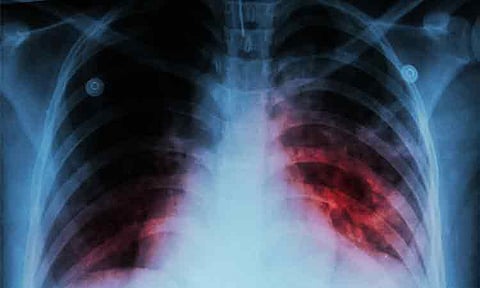

TB is an infectious disease primarily affecting the lungs, spread through the air when an infected person coughs, sneezes, or spits. However, it is preventable and curable.

Common symptoms include prolonged cough, chest pain, sudden weight loss, recurring fever, fatigue, and night sweats.